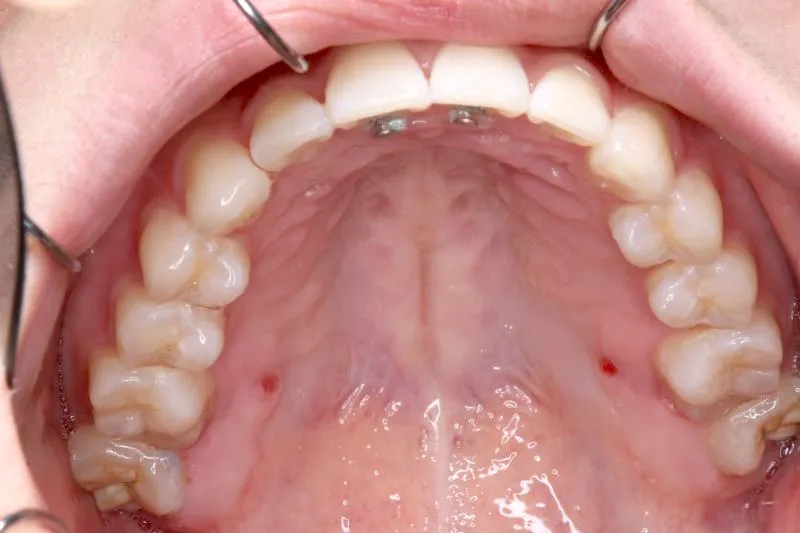

初診時

初診時年齢 小学校6年生 (女性) 主訴 犬歯がずれている・噛み合わない

診断名 叢生・交叉咬合 装置名

右下の犬歯がずれて生え噛み合わせの邪魔をしています。

歯は抜かず、上下マルチブラケット装置を使用し治療いたしました。